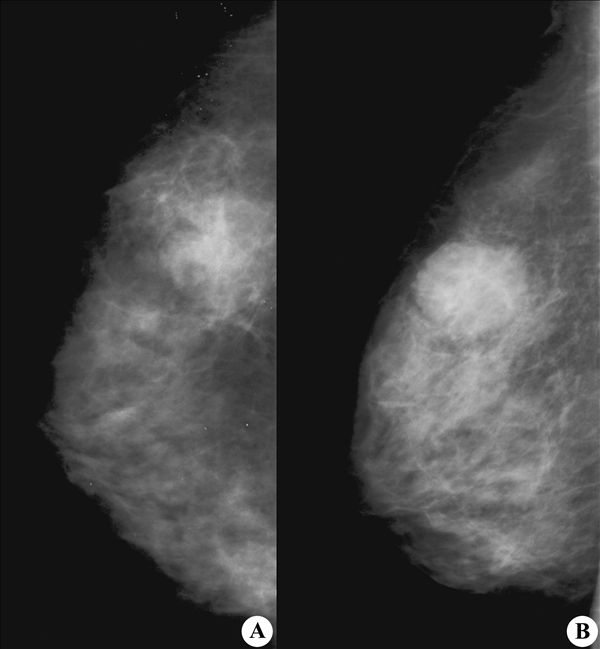

【X线钼靶摄影图片】:

【影像表现】:钼靶X线头尾位(A)及内外斜位(B)显示乳腺内肿块影,边缘见细小短毛刺,周围乳腺结构扭曲变形,部分向病灶内延伸。

【影像诊断】:乳腺癌1.